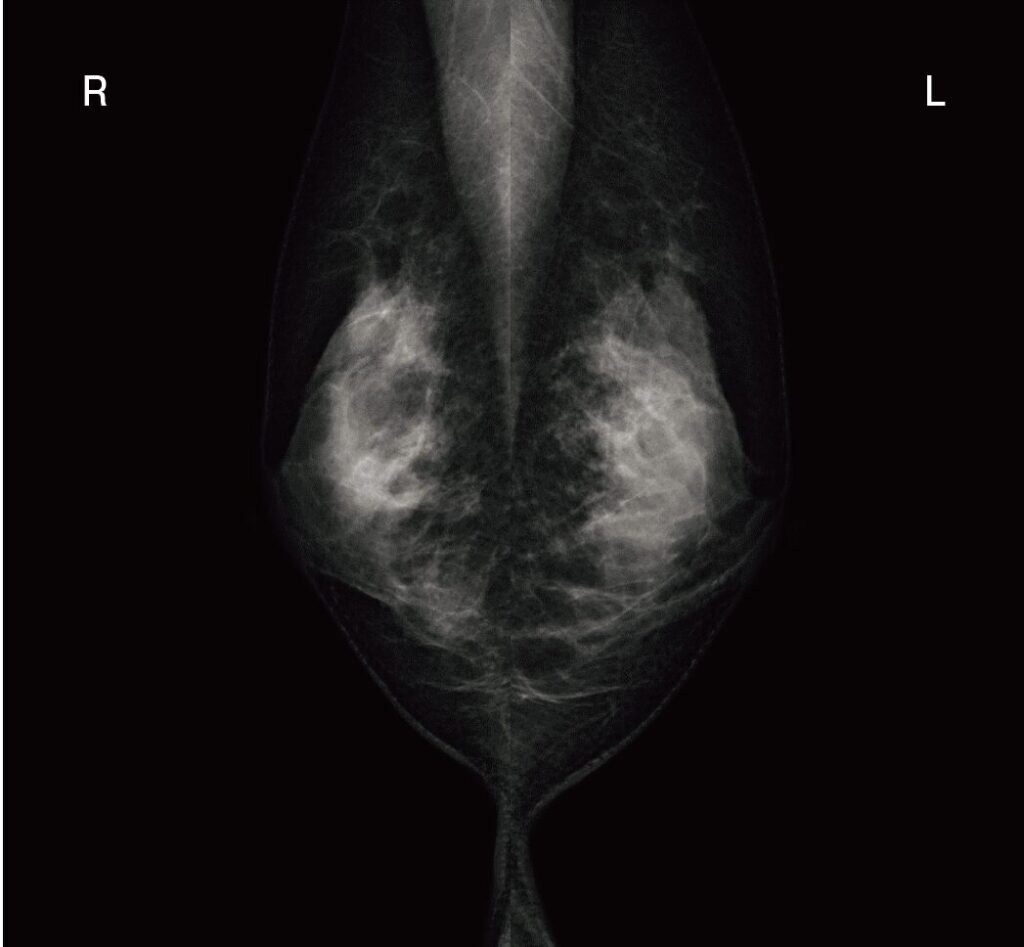

乳房X線写真を示す。この撮影法で正しいのはどれか。2つ選べ。

画面の上の方から、白っぽい筋肉(大胸筋)が斜め下に向かって「V字」のように入り込んでいます。そして、乳腺の下の方にはお腹のたるみ(乳房下溝)までしっかり写っています。

大胸筋がこのように斜めに広く写るのは「MLO(内外斜位方向:Mediolateral oblique)撮影」の特徴です。

- MLO撮影の画像:大胸筋が上から斜めに「V字」に入り込んでいる!